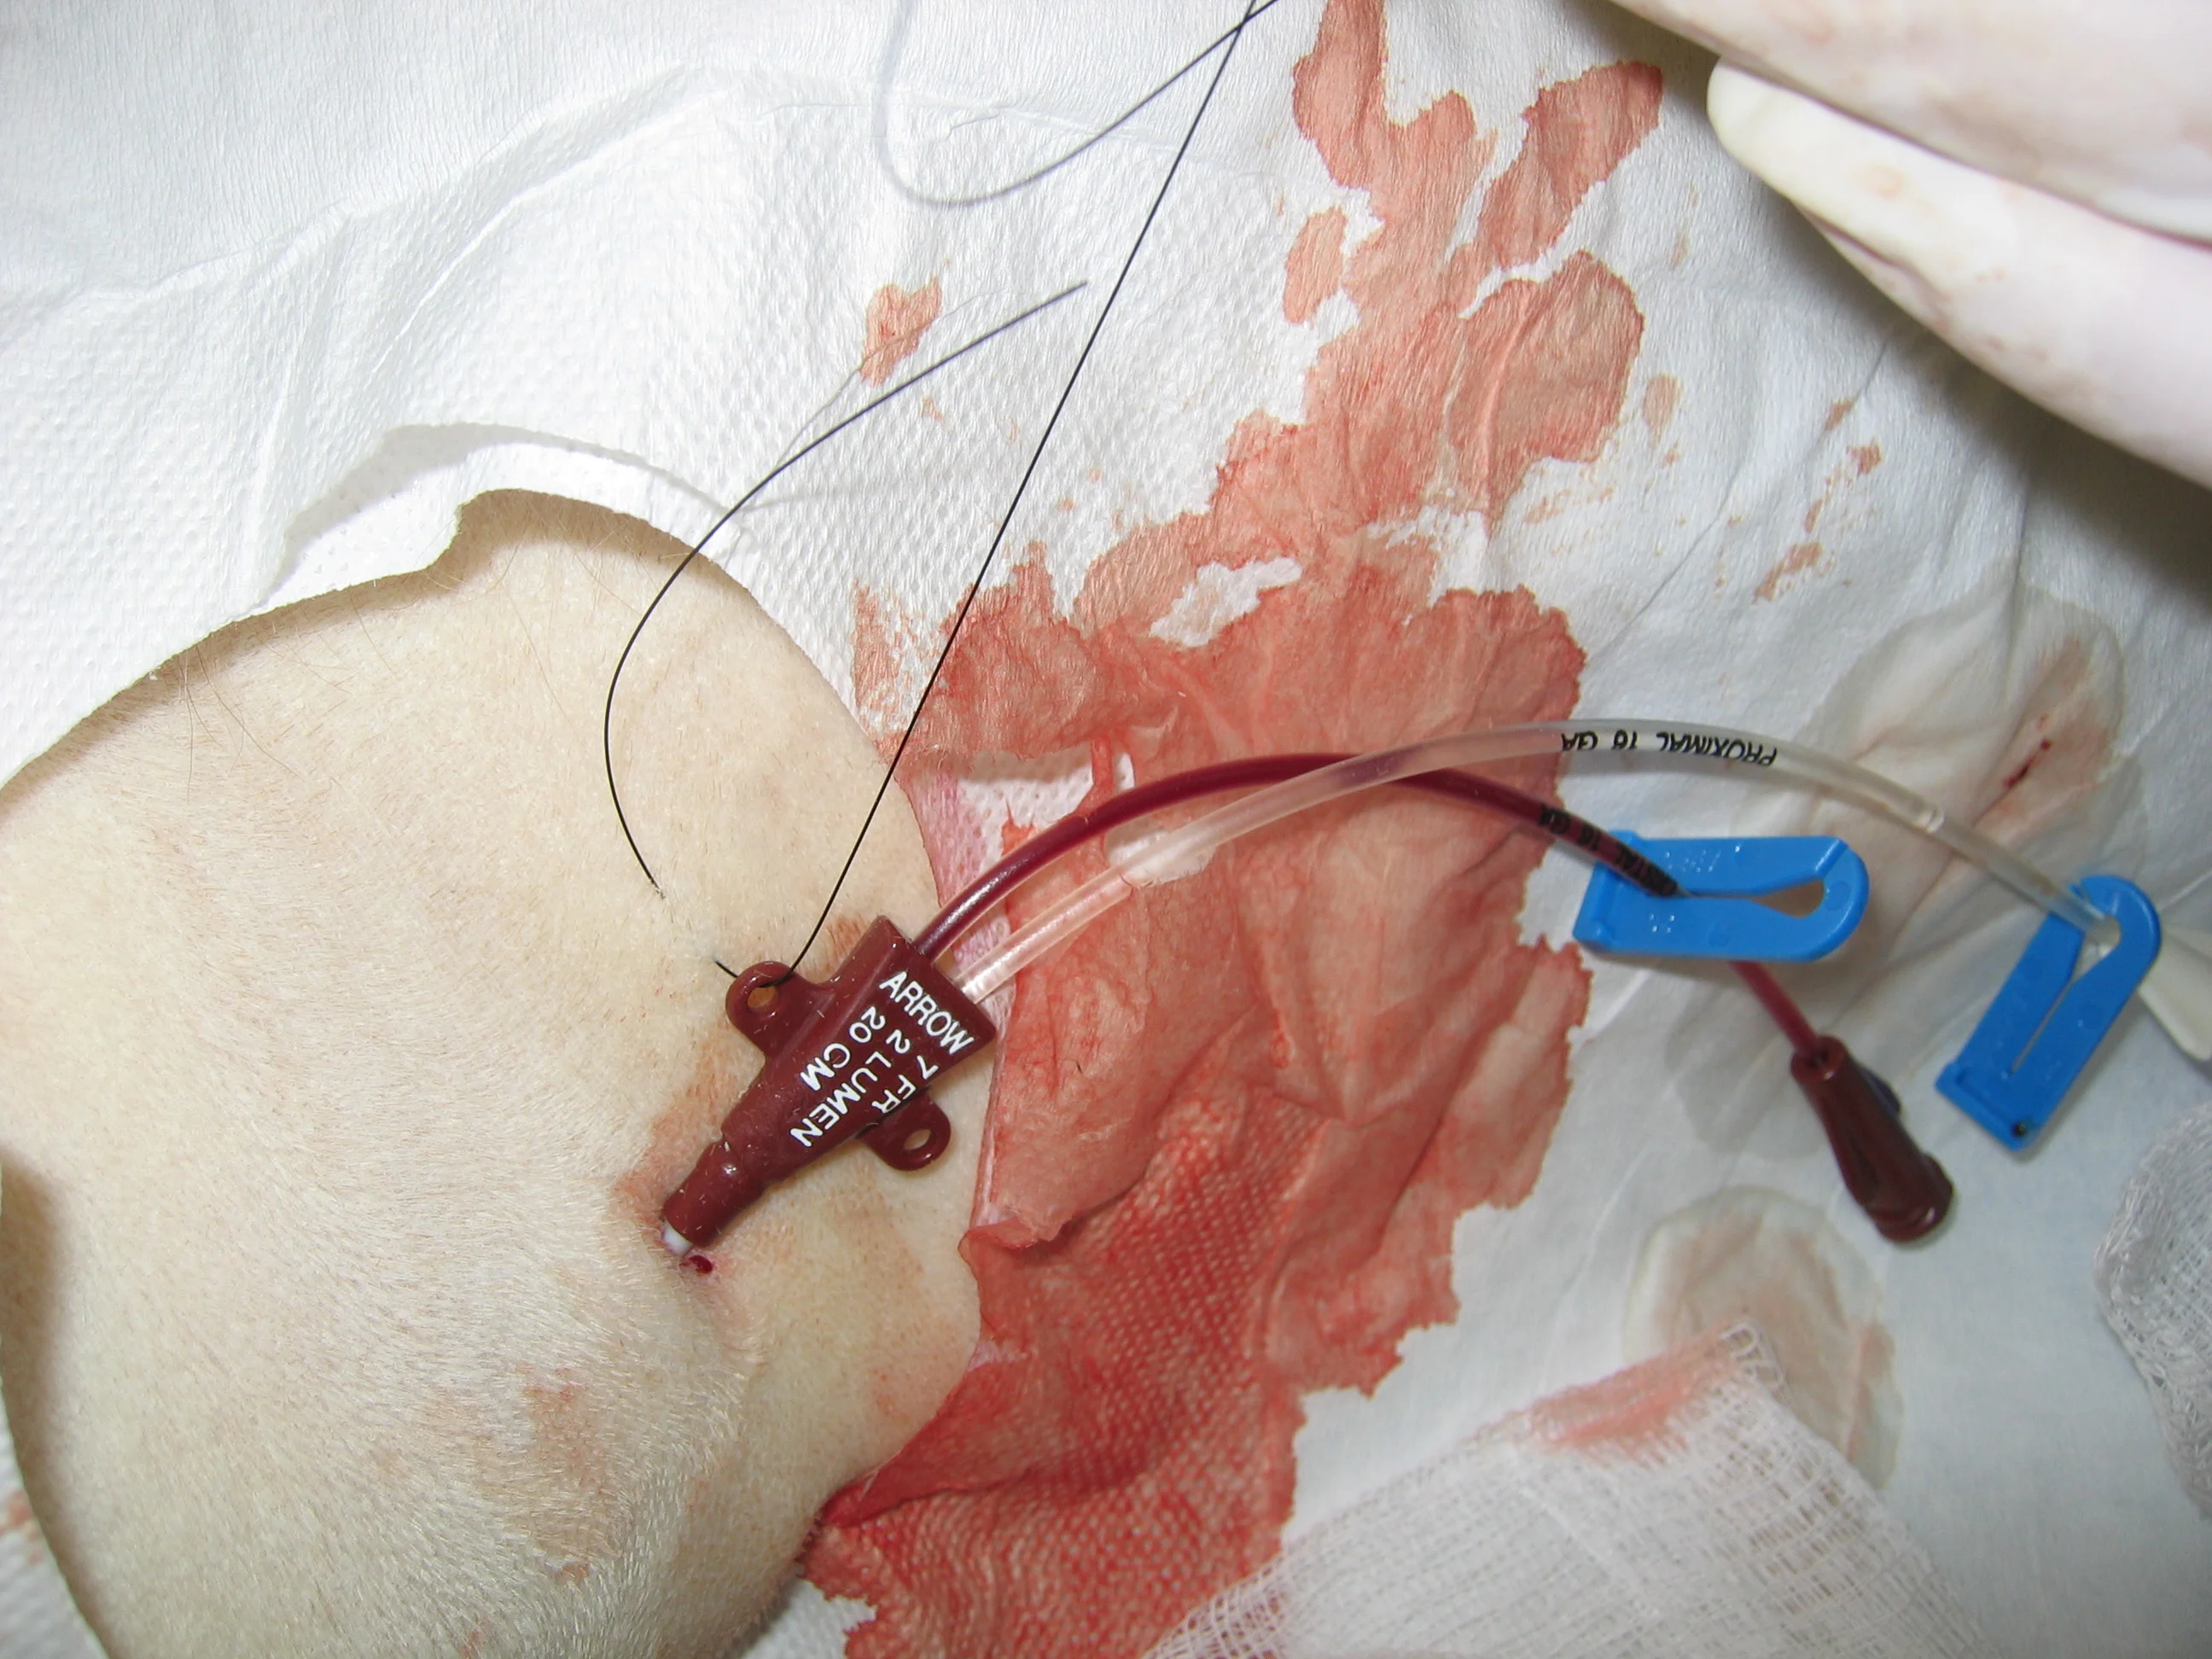

Step-by-Step: How to Place a Central Venous Catheter (Seldinger Technique)

The following step-by-step procedure discusses placement of a two-lumen, 7-French, 20-cm CVC (Arrow International, Reading, PA) via the right jugular vein in a dog. In the following series of images, the patient is always positioned in left lateral recumbency and the head is always to the right of the image.

Step 11

Suture the catheter in place at three anchor points. The "collar" of the catheter should be sutured in line with the jugular vein.

A red catheter is secured to the skin of an animal with sutures, indicating a clinical procedure involving intravenous access. The surrounding area is cleaned and prepared, showing signs of antiseptic application.